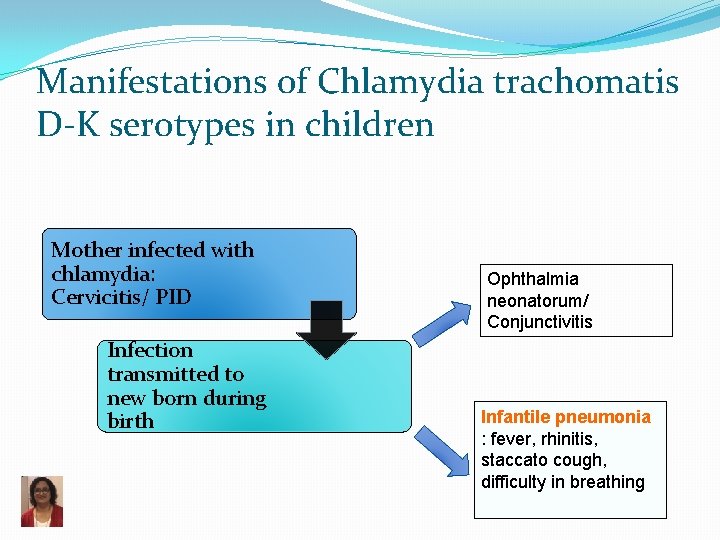

Manifestations of Chlamydia trachomatis D-K serotypes in children Mother infected with chlamydia: Cervicitis/ PID Infection transmitted to new born during birth Ophthalmia neonatorum/ Conjunctivitis Infantile pneumonia : fever, rhinitis, staccato cough, difficulty in breathing